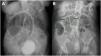

Case 1A 77-year-old woman, with a past medical history of high blood pressure and rheumatoid arthritis in treatment with an immunosuppressant, was admitted to the hospital due to community-acquired pneumonia and pleural effusion. Antimicrobial treatment was started, along with potassium replacement, given that moderate hypokalemia (2.9 mEq/l) was reported in the laboratory work-up. During hospitalization, she developed abdominal distension and constipation. CT showed generalized colonic dilatation (max. 10.1 cm), with no signs of mechanical obstruction (Fig. 1A). Conservative treatment with a TDT was given. Forty-eight hours later, the patient presented with improvement in abdominal distension, she passed gas, and her stools had no signs of inflammation, all of which was congruent with the decrease in the cecal dilatation shown in the control abdominal x-ray, compared with the initial diameter (Fig. 1B). Oral diet was restarted and treatment with polyethylene glycol, 17 g/day every 24 h, was begun to prevent recurrence. However, the patient presented with adult respiratory distress syndrome, causing her death.